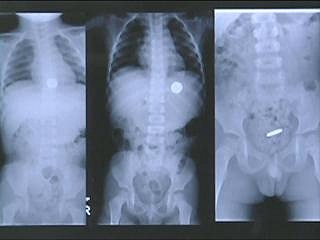

malchik proglotil skrepku i monetu odnako na rentgenovskom snimke obnaruzhilas interesnaya detal novosti rebenok malchik anomaliya obshestvo